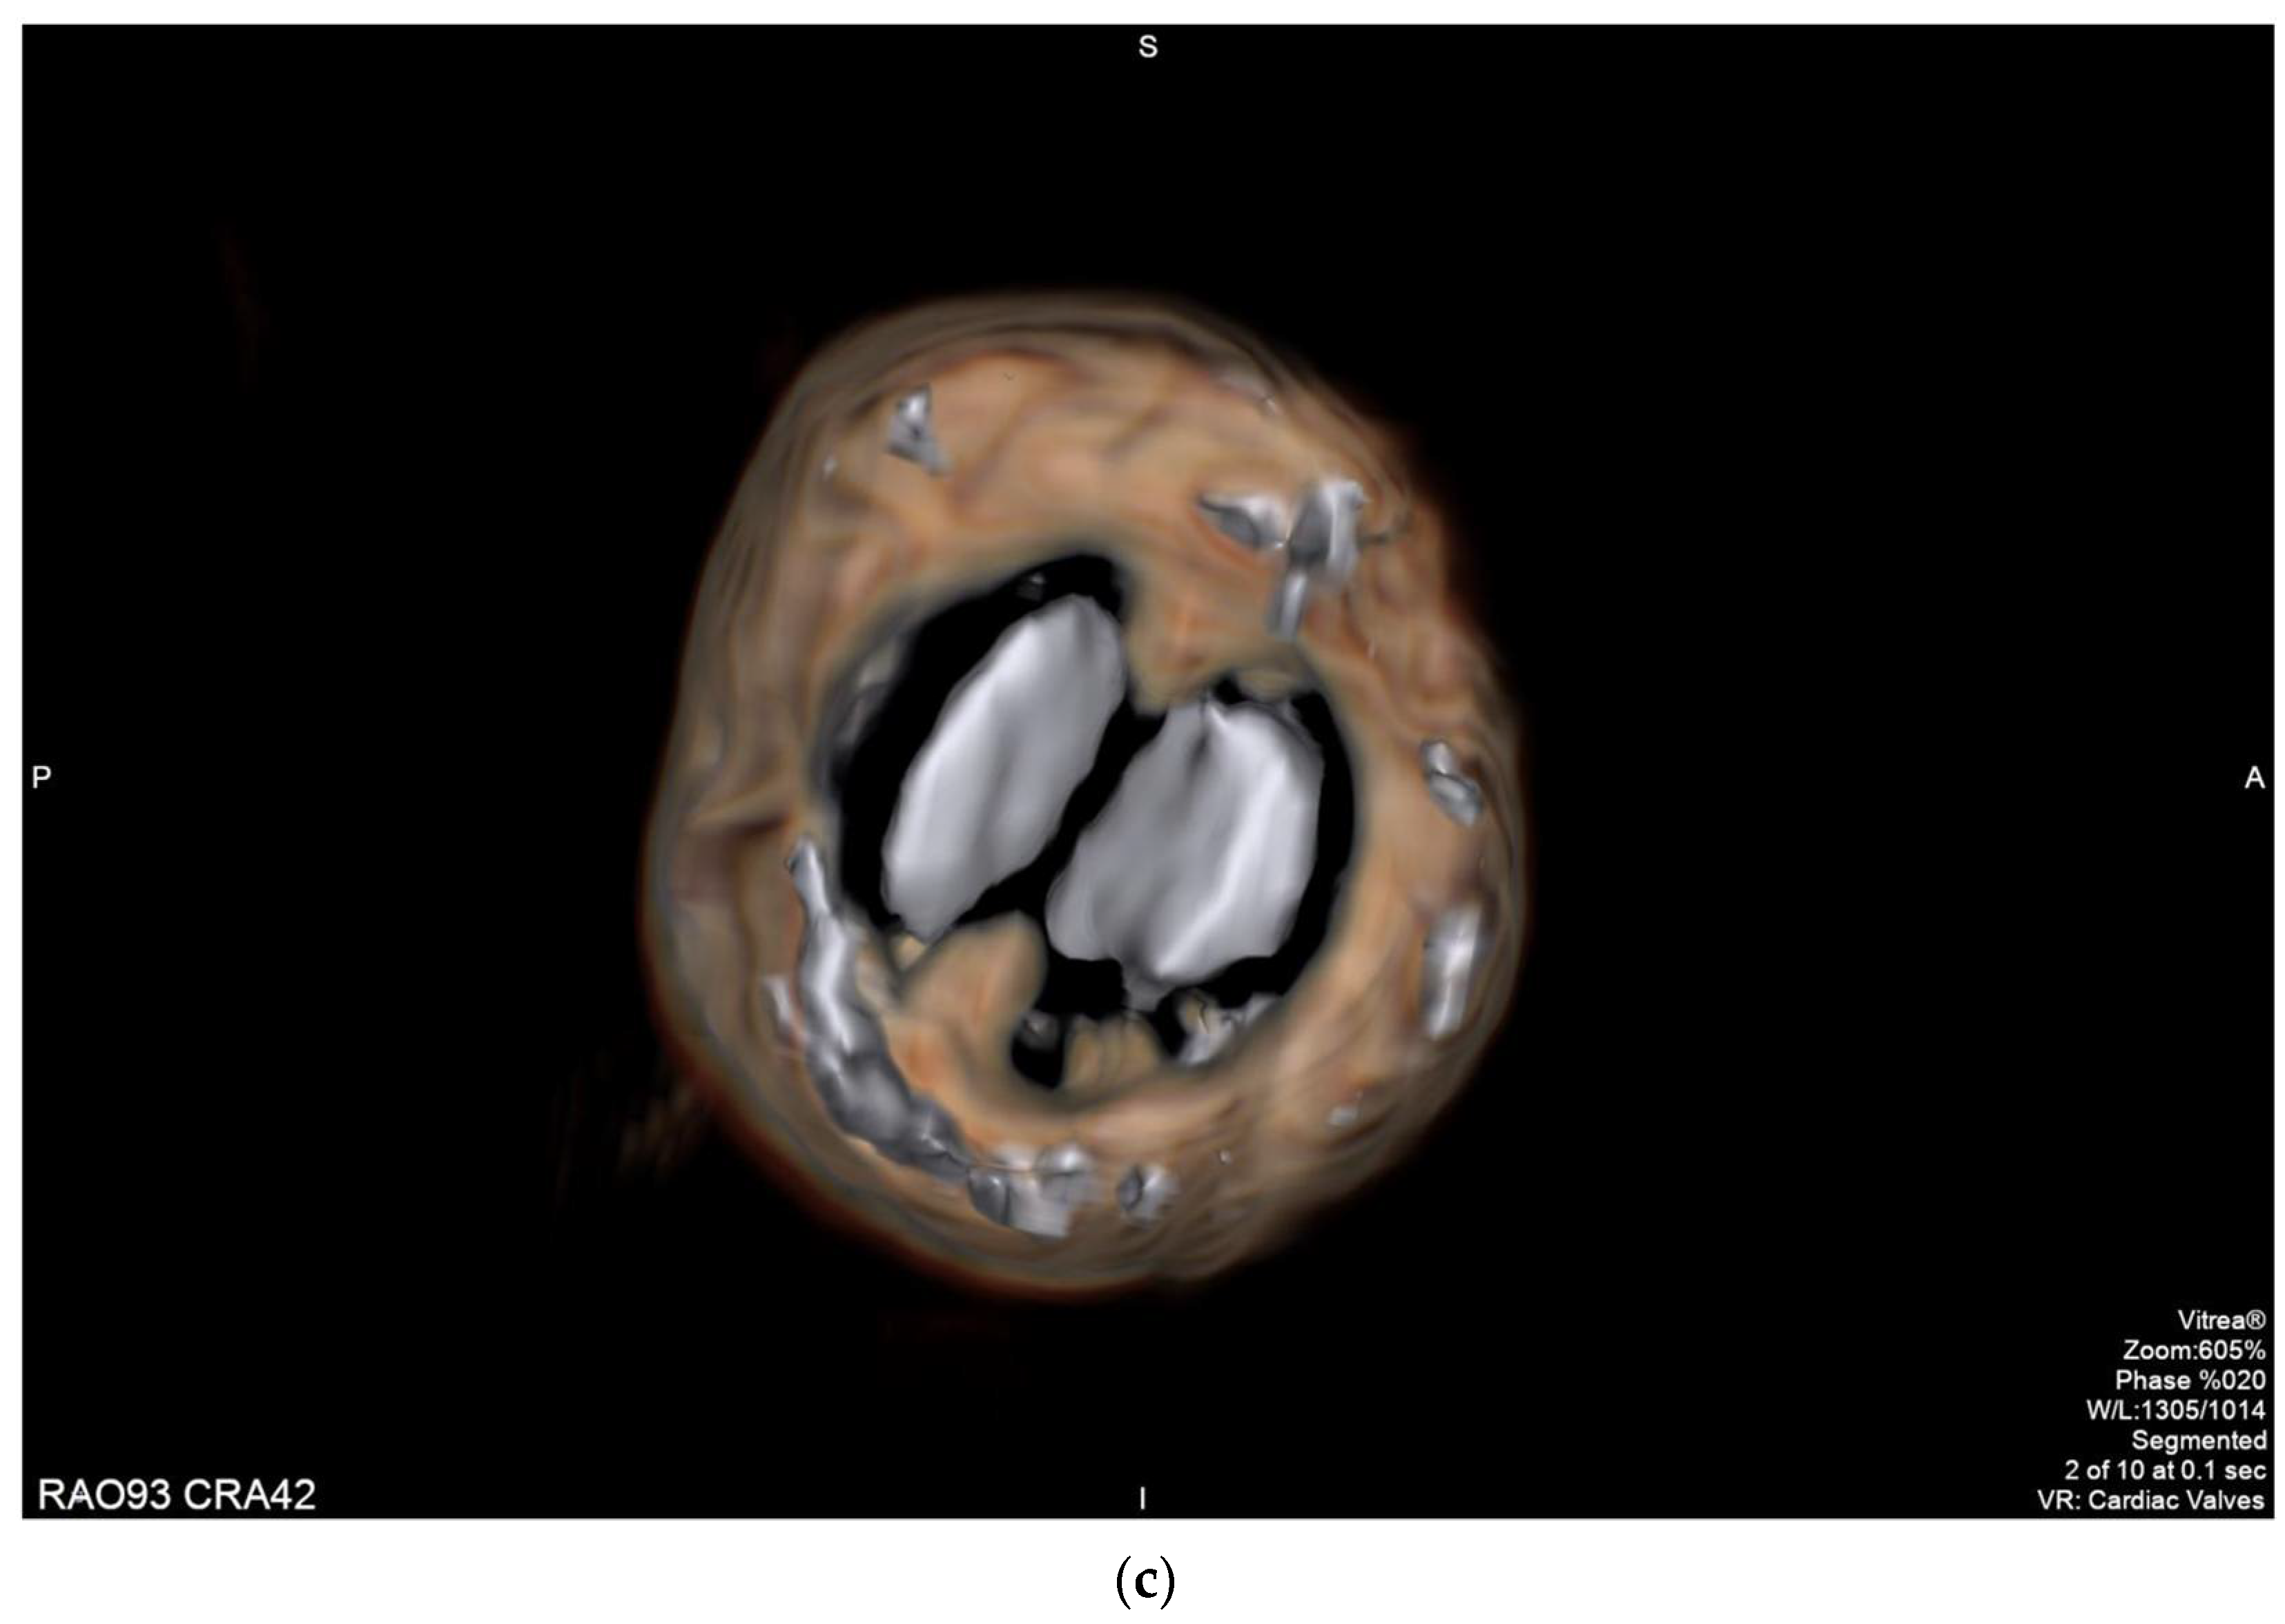

2.2. Case 2